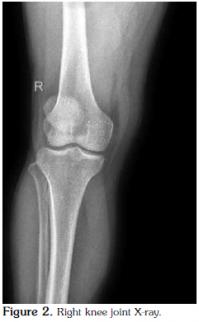

The patient was then admitted for further investigation. From an analytical point of view, there was an increase in acute phase reactants [C-reactive protein (CRP) 95.2 mg/L and erythrocyte sedimentation rate (ESR) 87 mm/hr]. Microcytic anemia was also present (hemoglobin 11.2 g/dL, mean erythrocyte volume 79.4 fl, and iron 37 mg/dl), but the ferritin and serum levels were normal as were the total iron binding capacity and transferrin saturation rate. Serum protein electrophoresis revealed a decrease in albumin (47.3%), whereas the alpha 1 (16.1%), alpha 2 (14.9%), and gamma globulin (21.3%) levels were higher. Other immunological tests determined that the rheumatoid factor (RF), anticyclic citrullinated peptide (anti-CCP), antinuclear antibody (ANA), complement, and anti-doublestranded deoxyribonucleic acid (anti-dsDNA) levels were normal, and the serum uric acid levels were also within normal limits. Furthermore, the primary and secondary tuberculosis screening tests were negative, and the serology tests for Brucella, Chlamydia, the human immunodeficiency virus (HIV), and hepatitis B and C were negative as well. Human leukocyte antigen typing revealed the presence of A1, A2, B41, B57, Cw6/7, DR11, and DR13 while a urinary system ultrasound and an intravenous pyelogram were normal. An X-ray of the pelvis showed degenerative changes (Figure 1), and because of the patient's ongoing lower back pain and peripheral joint swelling, magnetic resonance imaging (MRI) of the sacroiliac joints was performed, which showed periarticular edema of the sacrum in the anterior segment along with a slight increase in sclerosis of the right sacroiliac joint in the anterior superior segment. Slight edema of the left periarticular sacral area was also seen in the posterior segment. We then recommended that the MRI findings be interpreted in accordance with the clinical picture.